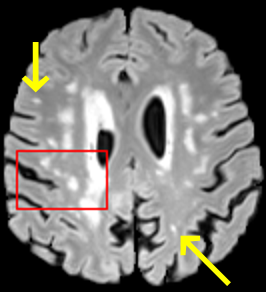

To test the impact of the iterative refinement on YODA’s translation quality, we compared regression and diffusion sampling on the RS data and present additional generation examples in Fig. 6. We observe that diffusion sampling visually resembles the appearance of the acquired images. Regression sampling preserves key anatomical features – the GM/WM boundary, WMHs (Fig. 4), the outline of the pallidum (Fig. 6) – but omits many high-frequency features. To investigate whether iterative refinement during diffusion sampling adds relevant and systematic medical information or only imitates acquisition noise, we performed ExpA sampling, i.e. averaging the output of several ( or ) diffusion trajectories. We observed a gradual loss of high-frequency details when increasing the (see also the supplementary video), indicating that the effect of the iterative refinement is non-systematic. For , the images are visually almost indistinguishable from the initial regression solution (see the supplementary video, and Fig.4 and 6). We directly compared the synthesis results of ExpA () and regression sampling quantitatively and found the differences to be minimal (SSIM: 99.73%, PSNR: 45.30 dB), i.e. diffusion sampling approaches the initial regression solution for a high . The quantitative analysis of the image quality (Tab. 1) showed that diffusion sampling impairs the assessed SSIM and PSNR in comparison to regression sampling for both the in- and external test sets, which we attribute to noise generation (Sec. 3.1). In turn, ExpA averages improved both metrics and, for , performed mostly on par with the regression solution in both test sets in terms of SSIM, while the PSNR in the RS was slightly increased (Tab. 1). However, we observed that ExpA sampling YODA improves the replication of systematic 3D low-frequency image intensity drifts (bias fields) due to the 3D synchronization in 2.5D diffusion sampling. Yet, this apparent advantage did not generalize to the external MBB dataset, as bias fields are MR protocol-specific.

We evaluated the impact of the proposed sampling methods on the performance of the independent, externally trained SHIVA-WMH tool as compared to manual reference labels (Tab. 1). Smoother images (higher or from regression sampling) yielded improved performance over those from diffusion sampling.

To assess the suitability of YODA-generated images for WMH detection independent of segmentation tools, we also calculated the CNR (15) of WMHs. This confirmed that the contrast of WMHs is preserved in the regression images, whereas we noted slightly reduced WMH contrast for diffusion and ExpA-sampled images (Tab. 1).

On the RS data (Tab. 1), regression sampling of YODA significantly outperformed all competing methods both w.r.t. the image quality and – except the ALVR for MADM – downstream WMH segmentation, whereas the DB of Choo et al. [31] achieved an higher WMH CNR.

When analyzing the RS synthesis results (Fig. 4), we noted that most reference methods strive to imitate realistic images, but several artifacts can be observed such as hallucinated WMHs (SynDiff) and salt-and-pepper noise (SynDiff, I2I-Mamba, ResViT).